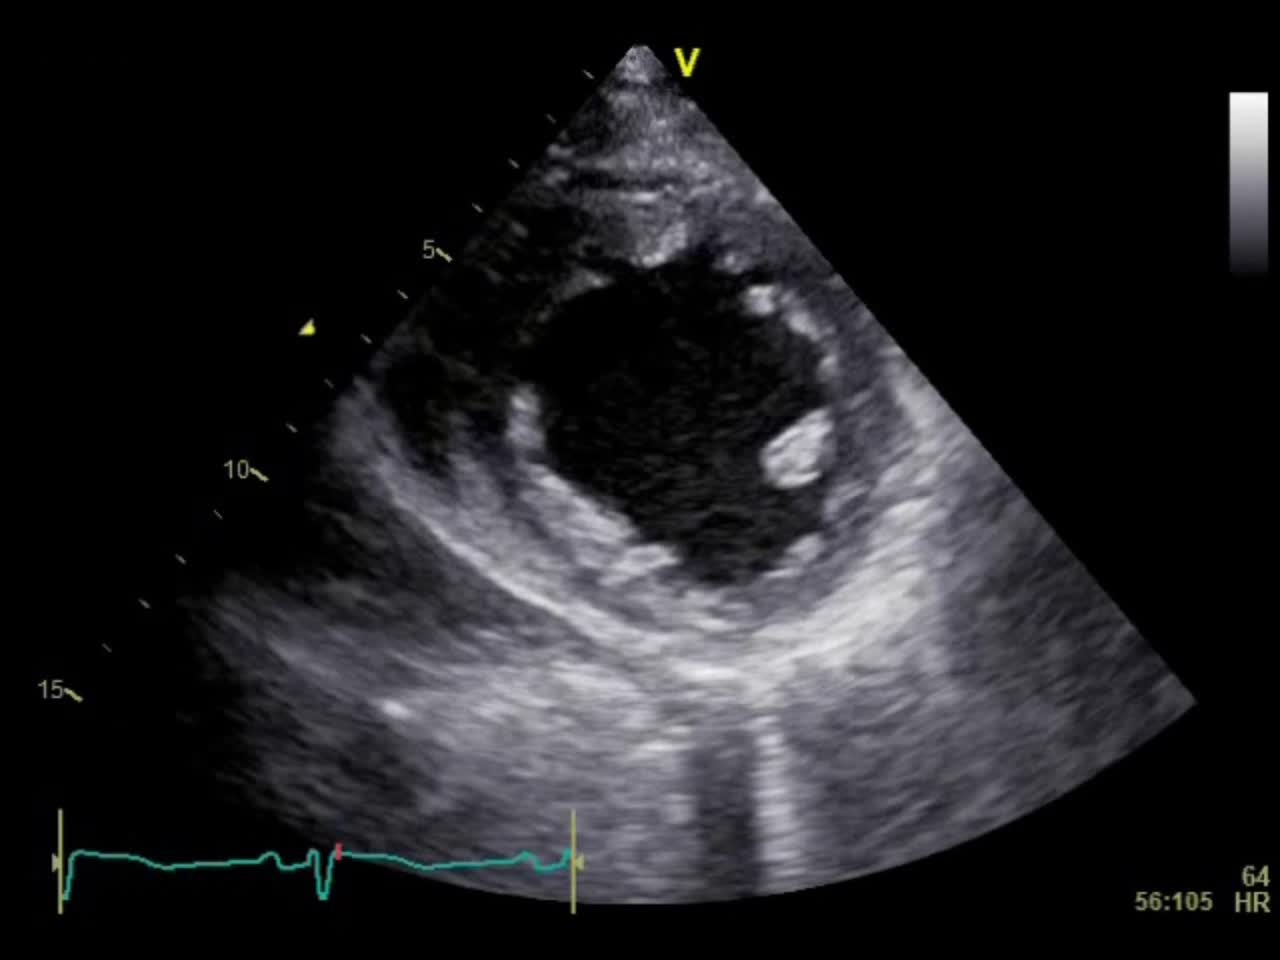

動画21-1 心エコー①(胸骨左縁短軸像)...

00:00:05